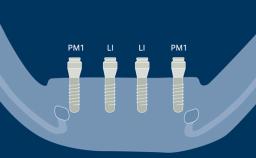

Prosthodontic Planning and Procedures

Implant Configurations for Fixed Dental Prostheses

Learning Module